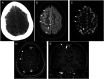

COVID-19 has been associated with central nervous system manifestations; however, cerebral venous thrombosis is rarely reported. A 34-year-old woman was admitted to the hospital with headache and recurrent seizures; she was recently discharged after COVID-19 pneumonia. Cranial magnetic resonance imaging and magnetic resonance venography showed cortical vein thrombosis in the right frontal lobe. SARS-CoV-2 RNA was detected in cerebrospinal fluid analysis. The patient was anticoagulated and put on antiepileptics. The most probable mechanism underlying the venous thrombosis is COVID-19-associated hypercoagulability. However, the relation between the viral RNA in cerebrospinal fluid analysis and the thrombosis is controversial.